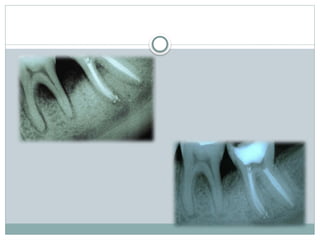

Diagnosis

Clinical diagnosis

Radiographic diagnosis

Glickman (1958)

Grade-I:

 Incipient or early stage of furcation involvement.

 Pocket is suprabony

 Radiographic changes are not usually found

Grade-II:

 can affect one or more of the furcation

of the same tooth

 Lesion is essentially a cul-de-sac, with

definite horizontal component

 Radiograph may or may not depict the

furcation involvement